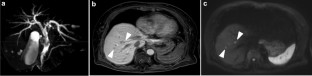

Recently, the number of reports describing patients with initially unresectable biliary tract cancer (BTC) who underwent resection in the form of conversion surgery is increasing. Gemcitabine plus cisplatin (GC) combination therapy has been reported to significantly prolong the median survival time from 8.1 to 11.7 months compared with conventional gemcitabine therapy in patients with unresectable BTC. We report the case of a patient with unresectable BTC who underwent conversion surgery with a partial response to GC combination therapy. A 78-year-old woman was diagnosed with unresectable BTC with invasion of the right hepatic artery by lymph node metastasis and liver metastases. The patient received GC combination therapy. After 6 cycles of chemotherapy, the patient achieved a partial response. The radiological findings revealed a marked shrinkage in the primary lesion and the disappearance of lymph node and liver metastases. Therefore, the patient underwent conversion surgery, including biliary tract resection and regional lymph node dissection. For postoperative follow-up, the patient was monitored without receiving adjuvant chemotherapy. The patient had not exhibited recurrence during the 12-month follow-up period. We report the case of a patient with unresectable BTC who underwent conversion surgery with a partial response to GC combination therapy.